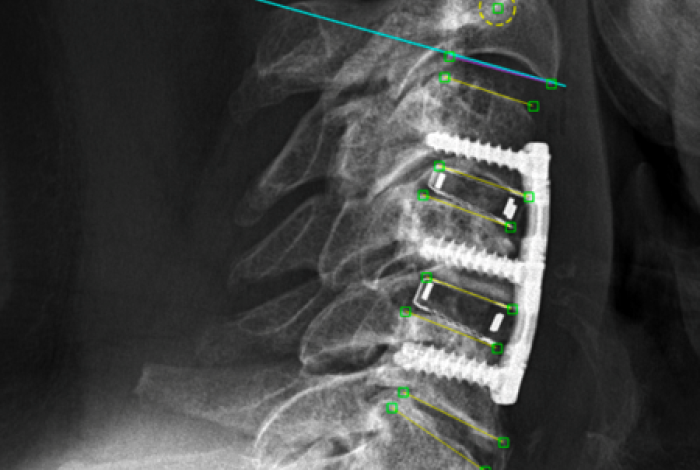

Forschung für die Wirbelsäule: Wenn Patientenerfahrungen vergleichbar werden

Um herauszufinden, wie es Patientinnen und Patienten nach Operationen geht, befragen wir sie seit über 20 Jahren mit speziellen Patientenfragebögen. Nun lassen sich erstmals die Resultate zweier verschiedener Fragebögen für die Halswirbelsäule vergleichen. Ein grosser Schritt für die Wirbelsäulenforschung, denn damit wächst das Wissen darüber, welche Operationen den Betroffenen wirklich helfen.